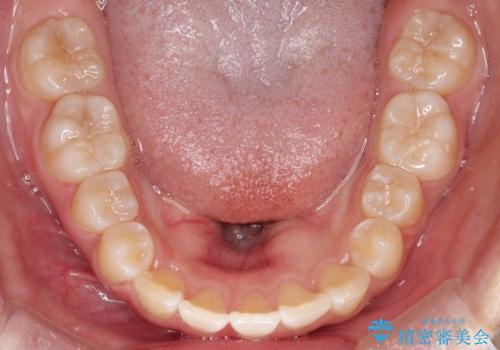

【インビザライン】前歯を下げたい

インビザラインにて奥歯の遠心移動を行いながら最大限前歯が下がるように治療を行いました。

今回は遠心移動とIPRによってここまで前歯を下げることができました。